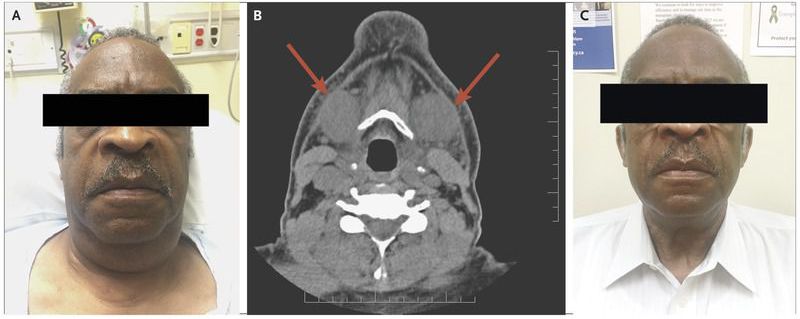

A 67-year-old man presented to the emergency department with neck swelling, dysphagia, and hoarseness that had started several hours after coronary angiography was performed. He had previously undergone heart transplantation owing to idiopathic dilated cardiomyopathy complicated by chronic kidney disease. He reported that he was allergic to contrast material and had therefore received hydrocortisone and diphenhydramine before the procedure. The physical examination was notable for enlargement and slight tenderness of the submandibular glands (Panel A). Computed tomography of the head and neck revealed symmetrically enlarged submandibular glands with no indication of stones or of fat stranding surrounding the glands (Panel B, arrows). The patient reported that he had experienced similar symptoms after previous exposure to iodinated contrast material, despite receiving medication before its administration. A diagnosis of iodide-associated sialadenitis was made. Iodide-associated sialadenitis is rare and is believed to result from an elevated concentration of iodine in the saliva, which causes swelling of the mucosal duct and impaired salivary excretion. The risk of sialadenitis may be increased by impaired renal function owing to impaired clearance of iodinated contrast material. Sialadenitis is typically benign and resolves within days without treatment. Since sialadenitis is not an allergic phenomenon, the condition cannot be prevented with premedication. The patient’s symptoms resolved completely after 5 days (Panel C).